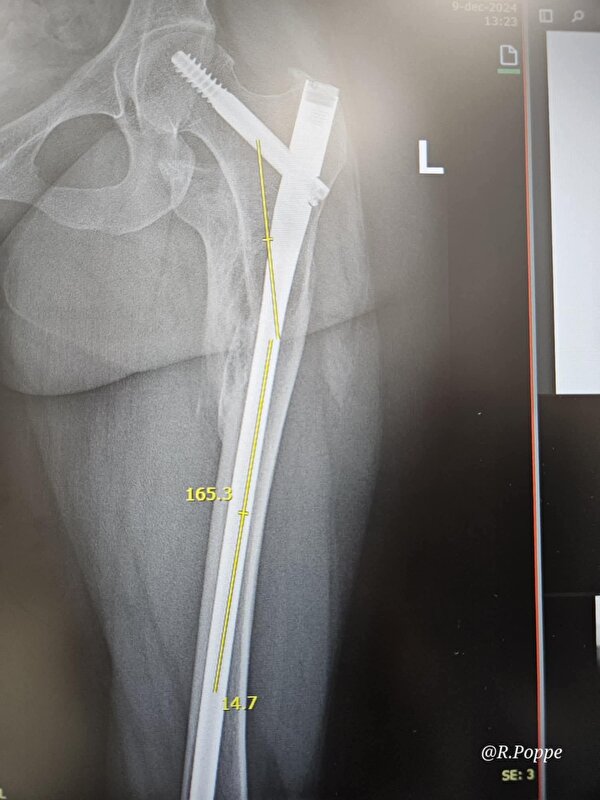

Bij de eerste drafpas meteen al veel pijn, dus ik heb er een stapritje van gemaakt. Met brace om heb ik daar geen last van dus komende week maar eens proberen en hopen dat hij niet schrikt van het gepiep